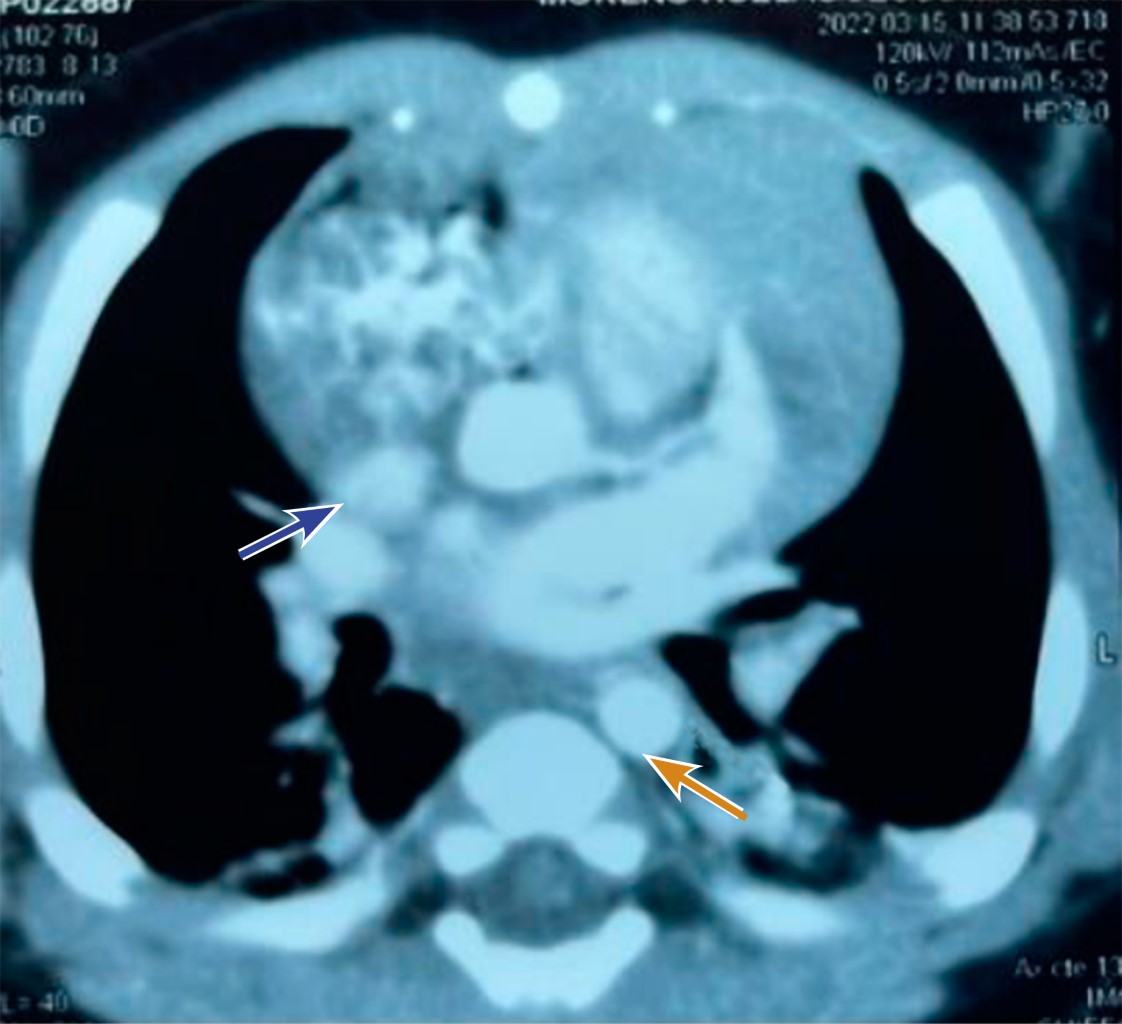

Intracardiac hemangioma in an infant

Introduction: intracardiac tumors in children are rare, but most are benign. In general, these tumors do not cause symptoms, but as they increase in size, they can lead to heart failure. Case presentation: three-month-old male patient who had an intrauterine diagnosis of mediastinal mass. At birth he was asymptomatic. Resection of right atrial tumor was performed. The pathology report indicated that it was an intracardiac hemangioma. The patient has had a favorable evolution. Conclusions: intracardiac tumors are a rare entity in pediatrics, which are generally detected accidentally.

Figure 2